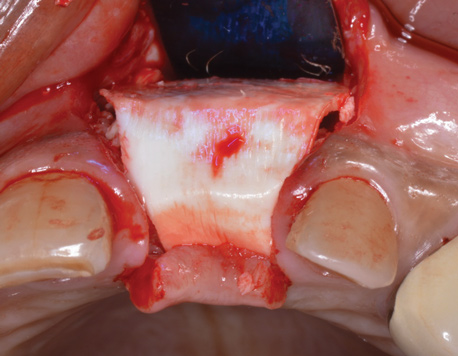

(15.) Due to physiologic remodeling of the alveolar ridge, facially inclined implant positions, and ineffective augmentation at time of placement, these three implants are experiencing mucosal recession.

Figure 15

(16.) Following flap reflection, the buccal bone deficiencies are evident.

Figure 16